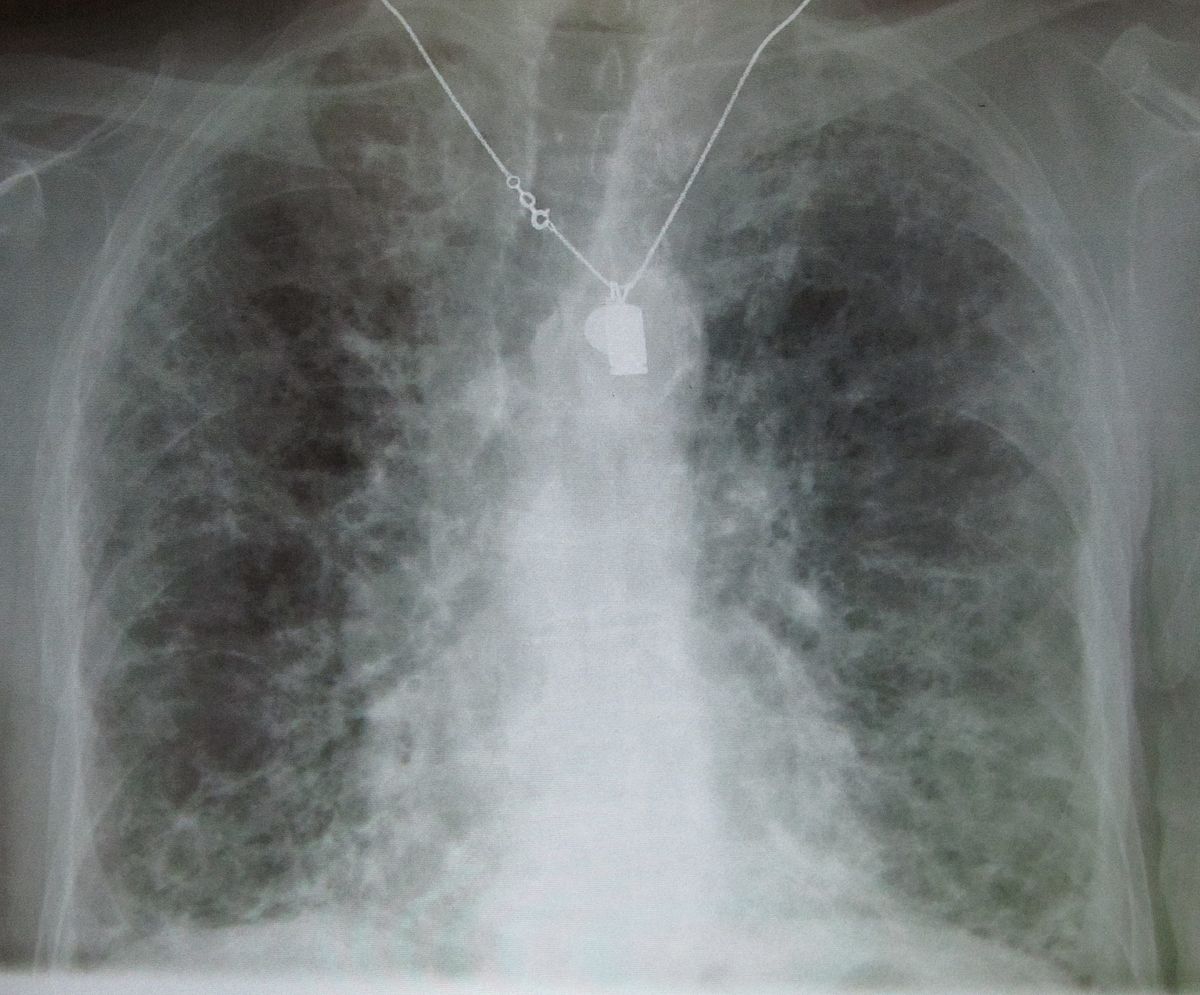

Fibrosi polmonari, Di Marco (Boehringer): Devastanti come tumori